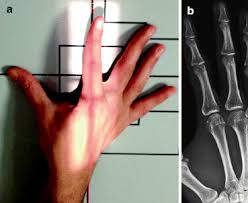

in regards to the 2nd-5th digits, what are the 3 Phalanges (3)? (name them and picture where they go)

Distal, Middle, Proximal

in regards to the 2nd-5th digits, what are their Joints(2)? (name them and picture where they go)

Distal Interphalangeal Joint, Proximal Interphalangeal Joint

in regards to the 1st digits, what are their Phalanges (2)? (name them and picture where they go)

Distal, Proximal